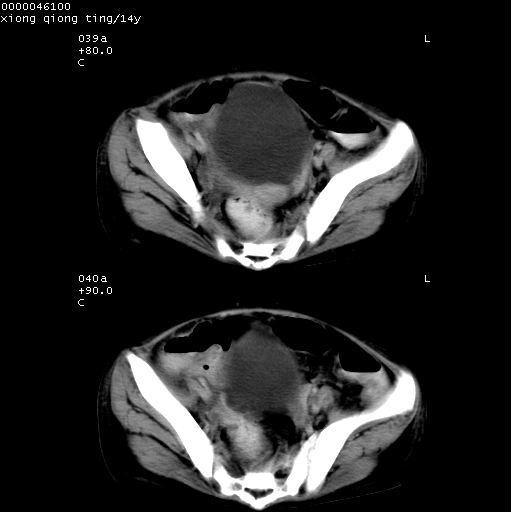

腹部b超提示:子宫缩小,盆腔积液,肝实质回声密集。

中下腹及盆腔ct轴位平扫+增强扫描(层厚10mm,螺距1.0,重建间隔10mm),图像如下:

(注:患儿检查当日上午9时口服胃肠道对比剂,下午3时许行ct扫描检查,未行对比剂直肠保留灌肠,检查当日患儿腹泻)

中下腹及盆腔ct轴位扫描(ps+ce)提示:腹部肠管明显充气扩张,并见数个不同宽度之气液平面;疑不全性肠梗阻或肠郁张。临床会诊考虑为患儿腹泻,肠郁张所致;后来未经特殊处理,患儿大便恢复正常,亦无腹胀。

临床出院诊断:1)结核性腹膜炎。2)腹膜后淋巴结结核。3)脂肪肝。